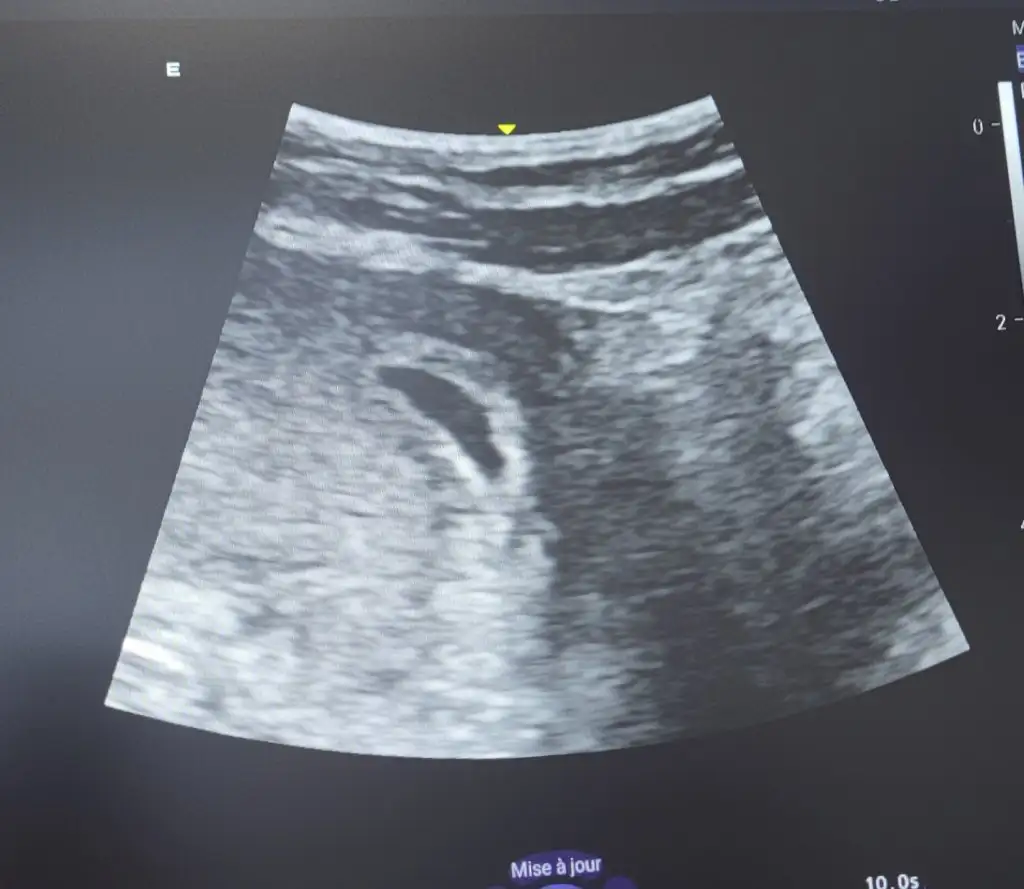

Benim keseme çok benziyorEki Görüntüle 3379989 bu da benim kesem kızlar. Bir ṣey gözükmüyor ama bebiṣ var mıṣ. Fasulyeee

Keseler. Benzer fasulyeye erkek diyolar benim ki ne kadar cevirdiyse yuvarlak durdu hepBenim keseme çok benziyor

Kızımın kesesi baya yuvarlak bu fasülye bakalım gönlümüzdeki olur inşallah konu açmıştım ben 2 keseyi atmıştım konuma bakabilirsin istersen seninkine benziyor muKeseler. Benzer fasulyeye erkek diyolar benim ki ne kadar cevirdiyse yuvarlak durdu hep

Kız gözükmüyor bulamadımKızımın kesesi baya yuvarlak bu fasülye bakalım gönlümüzdeki olur inşallah konu açmıştım ben 2 keseyi atmıştım konuma bakabilirsin istersen seninkine benziyor mu